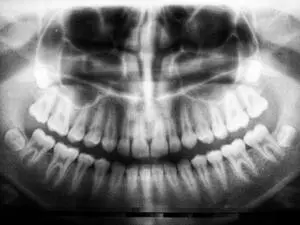

Some dental professionals recommend the removal of wisdom teeth to prevent future problems. If X-rays show that they are impacted, positioned at an odd angle, or will cause overcrowding, they can be removed before any pain or infection sets in. The procedure is best done at a younger age. Ideally, surgery is scheduled before the jawbone hardens with age and the teeth are difficult to remove.